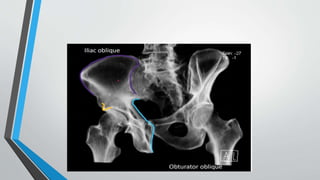

JUDATEVIEW

Types:

I. Obturator oblique

II. Iliac oblique

• Oriented 45 degrees to coronal plane

• Obturator ring is perpendicular (orthogonal) to iliac wing

• Iliac oblique of one hip is obturator oblique of contralateral hip

ii.Iliac oblique

• Contralateral (uninjured) hemipelvis bumped up, toward Xray beam

• Exposes surface of the iliac wing

• Obturator foramen not visible, obturator ring as thin as possible

• Best demonstrates

1) Posterior column 2) Anterior wall 3) Iliac wing in profile